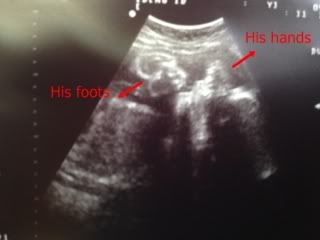

Oh ya , before I forgotten , I also uploaded one u/s picture during 7 months+ checkup . Only uploaded one cause the rest of the u/s, I can't figured out which part is which part.

Here is it :

As you guys can see that my baby boy seems to squeeze himself into a ball , I guess not much space for him , that's why his legs are folded up . Feel quite guilty about it (although is not my fault ) I wonder will he get cramp ? hmm.

Ever since I entered 3rd trimester, my baby boy loves to place his foot at my left side of my belly that is the reason why I always got a hard bump on my left side.